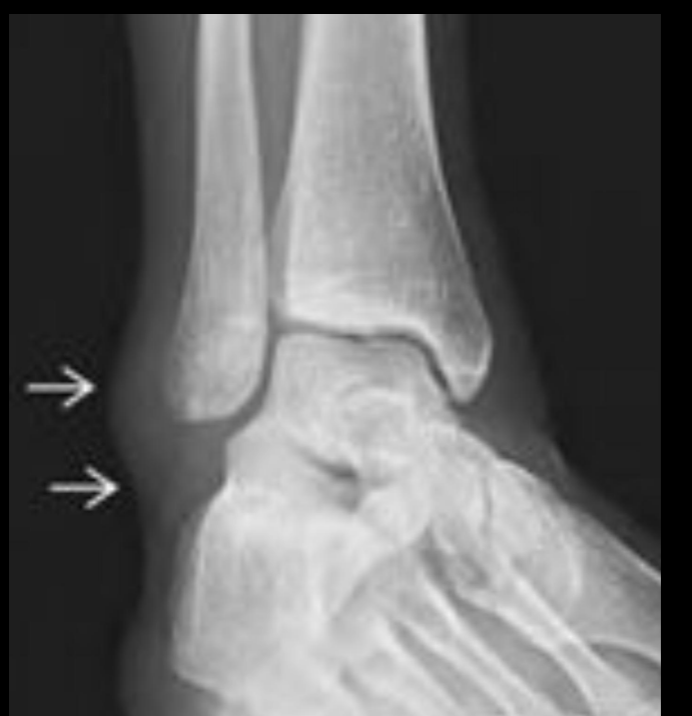

Rx en esguince de tobillo

Edema de tejidos blandos

Aumento del espacio entre perone y astragalo

Como pedir Rx en esguince de tobillo?

Con estrés

A

Rx esguince